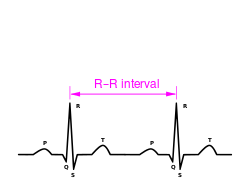

القياس الإلكتروني

وهناك طريقة أكثر دقة لتحديد معدل ضربات القلب تنطوي على استخدام تخطيط كهربائية القلب (ECG). يوّلد تخطيط القلب نمطًا يعتمد على النشاط الكهربائي للقلب، والذي يتبع وظيفة القلب. يتم إجراء رصد مستمر لتخطيط القلب بشكل روتيني في العديد من الأماكن السريرية، وخاصة في العناية المركزة. حيث يتم حساب معدل ضربات القلب لحظيًا باستخدام فاصل من الموجة R إلى الموجة R، وضرب / قسمة من أجل اشتقاق معدل ضربات القلب بنبضات القلب / دقيقة. وتوجد طرق متعددة هي:

- معدل ضربات القلب = 1،500 / (الفاصل الزمني RR في ملليمتر)

- معدل ضربات القلب = 60 / (فترة RR في ثوان)

- معدل ضربات القلب = 300 / عدد المربعات "الكبيرة" بين موجات R المتعاقبة.

- معدل ضربات القلب = 1.500 مجموعة كبيرة